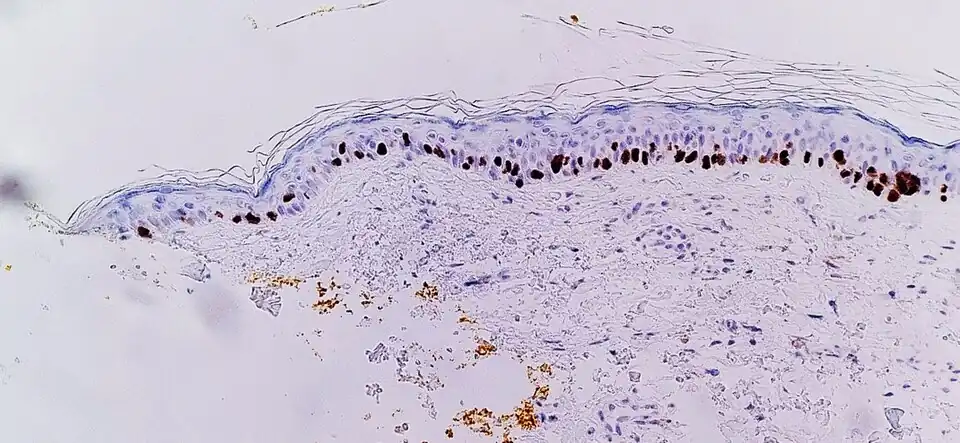

Immunohistochemistry with SOX10 (staining the cell nuclei of melanocytes) facilitates diagnosis of lentigo maligna, in this case showing an increased number of melanocytes along stratum basale of the skin, and nuclear pleomorphism. The changes are continuous with the resection margin (inked in yellow, at left), conferring a diagnosis of a not radically removed lentigo maligna.

Immunohistochemistry with SOX10 (staining the cell nuclei of melanocytes) facilitates diagnosis of lentigo maligna, in this case showing an increased number of melanocytes along stratum basale of the skin, and nuclear pleomorphism. The changes are continuous with the resection margin (inked in yellow, at left), conferring a diagnosis of a not radically removed lentigo maligna. -